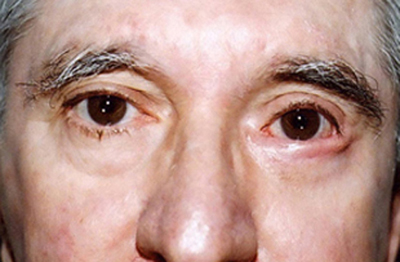

Venimos realizando esta técnica quirúrgica desde hace 10 años, los resultados en un total de 14 pacientes han sido satisfactorios, con mejoría en todos los casos. Operamos seis pacientes de ambos ojos y ocho de uno solo, seis pacientes femeninos y ocho masculinos, con edades entre los 50 y 82 años, con un promedio de 66.7. No hemos tenido ninguna pérdida del injerto, en dos casos nos quedamos un poco hipo corregídos, por laxitud horizontal palpebral, que con una técnica suplementaria de menor complejidad ( fijación cantal lateral) se lograron solucionar. (Figura 6, 7, 8 y 9)

Figura 6 Pre-operatorio

Figura 7 Pre-operatorio

Figura 8 Post-operatorio 12 meses

Figura 9 Post-operatorio 6 meses